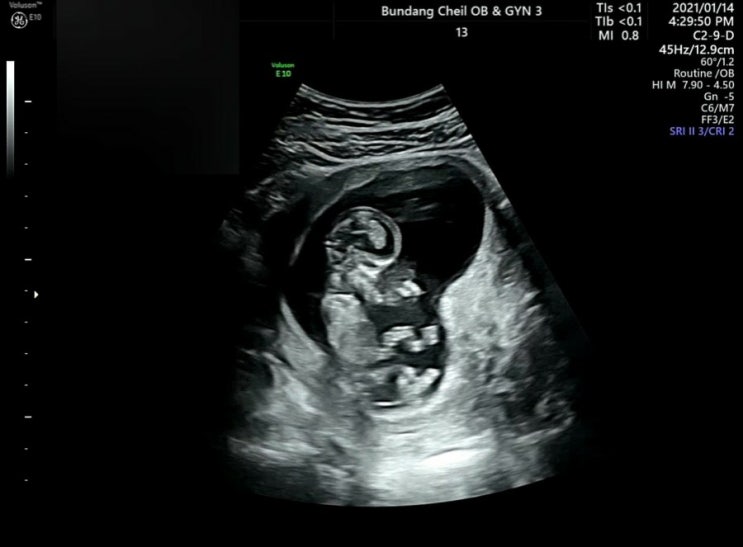

[11주6일]분당제일여성병원/1차기형아검사/입체초음파

임테기 두 줄을 확인하고 긴가민가하며 설레어 하던게 엊그제 같은데 벌써 임신 12주가 가까워 오고 있어요...